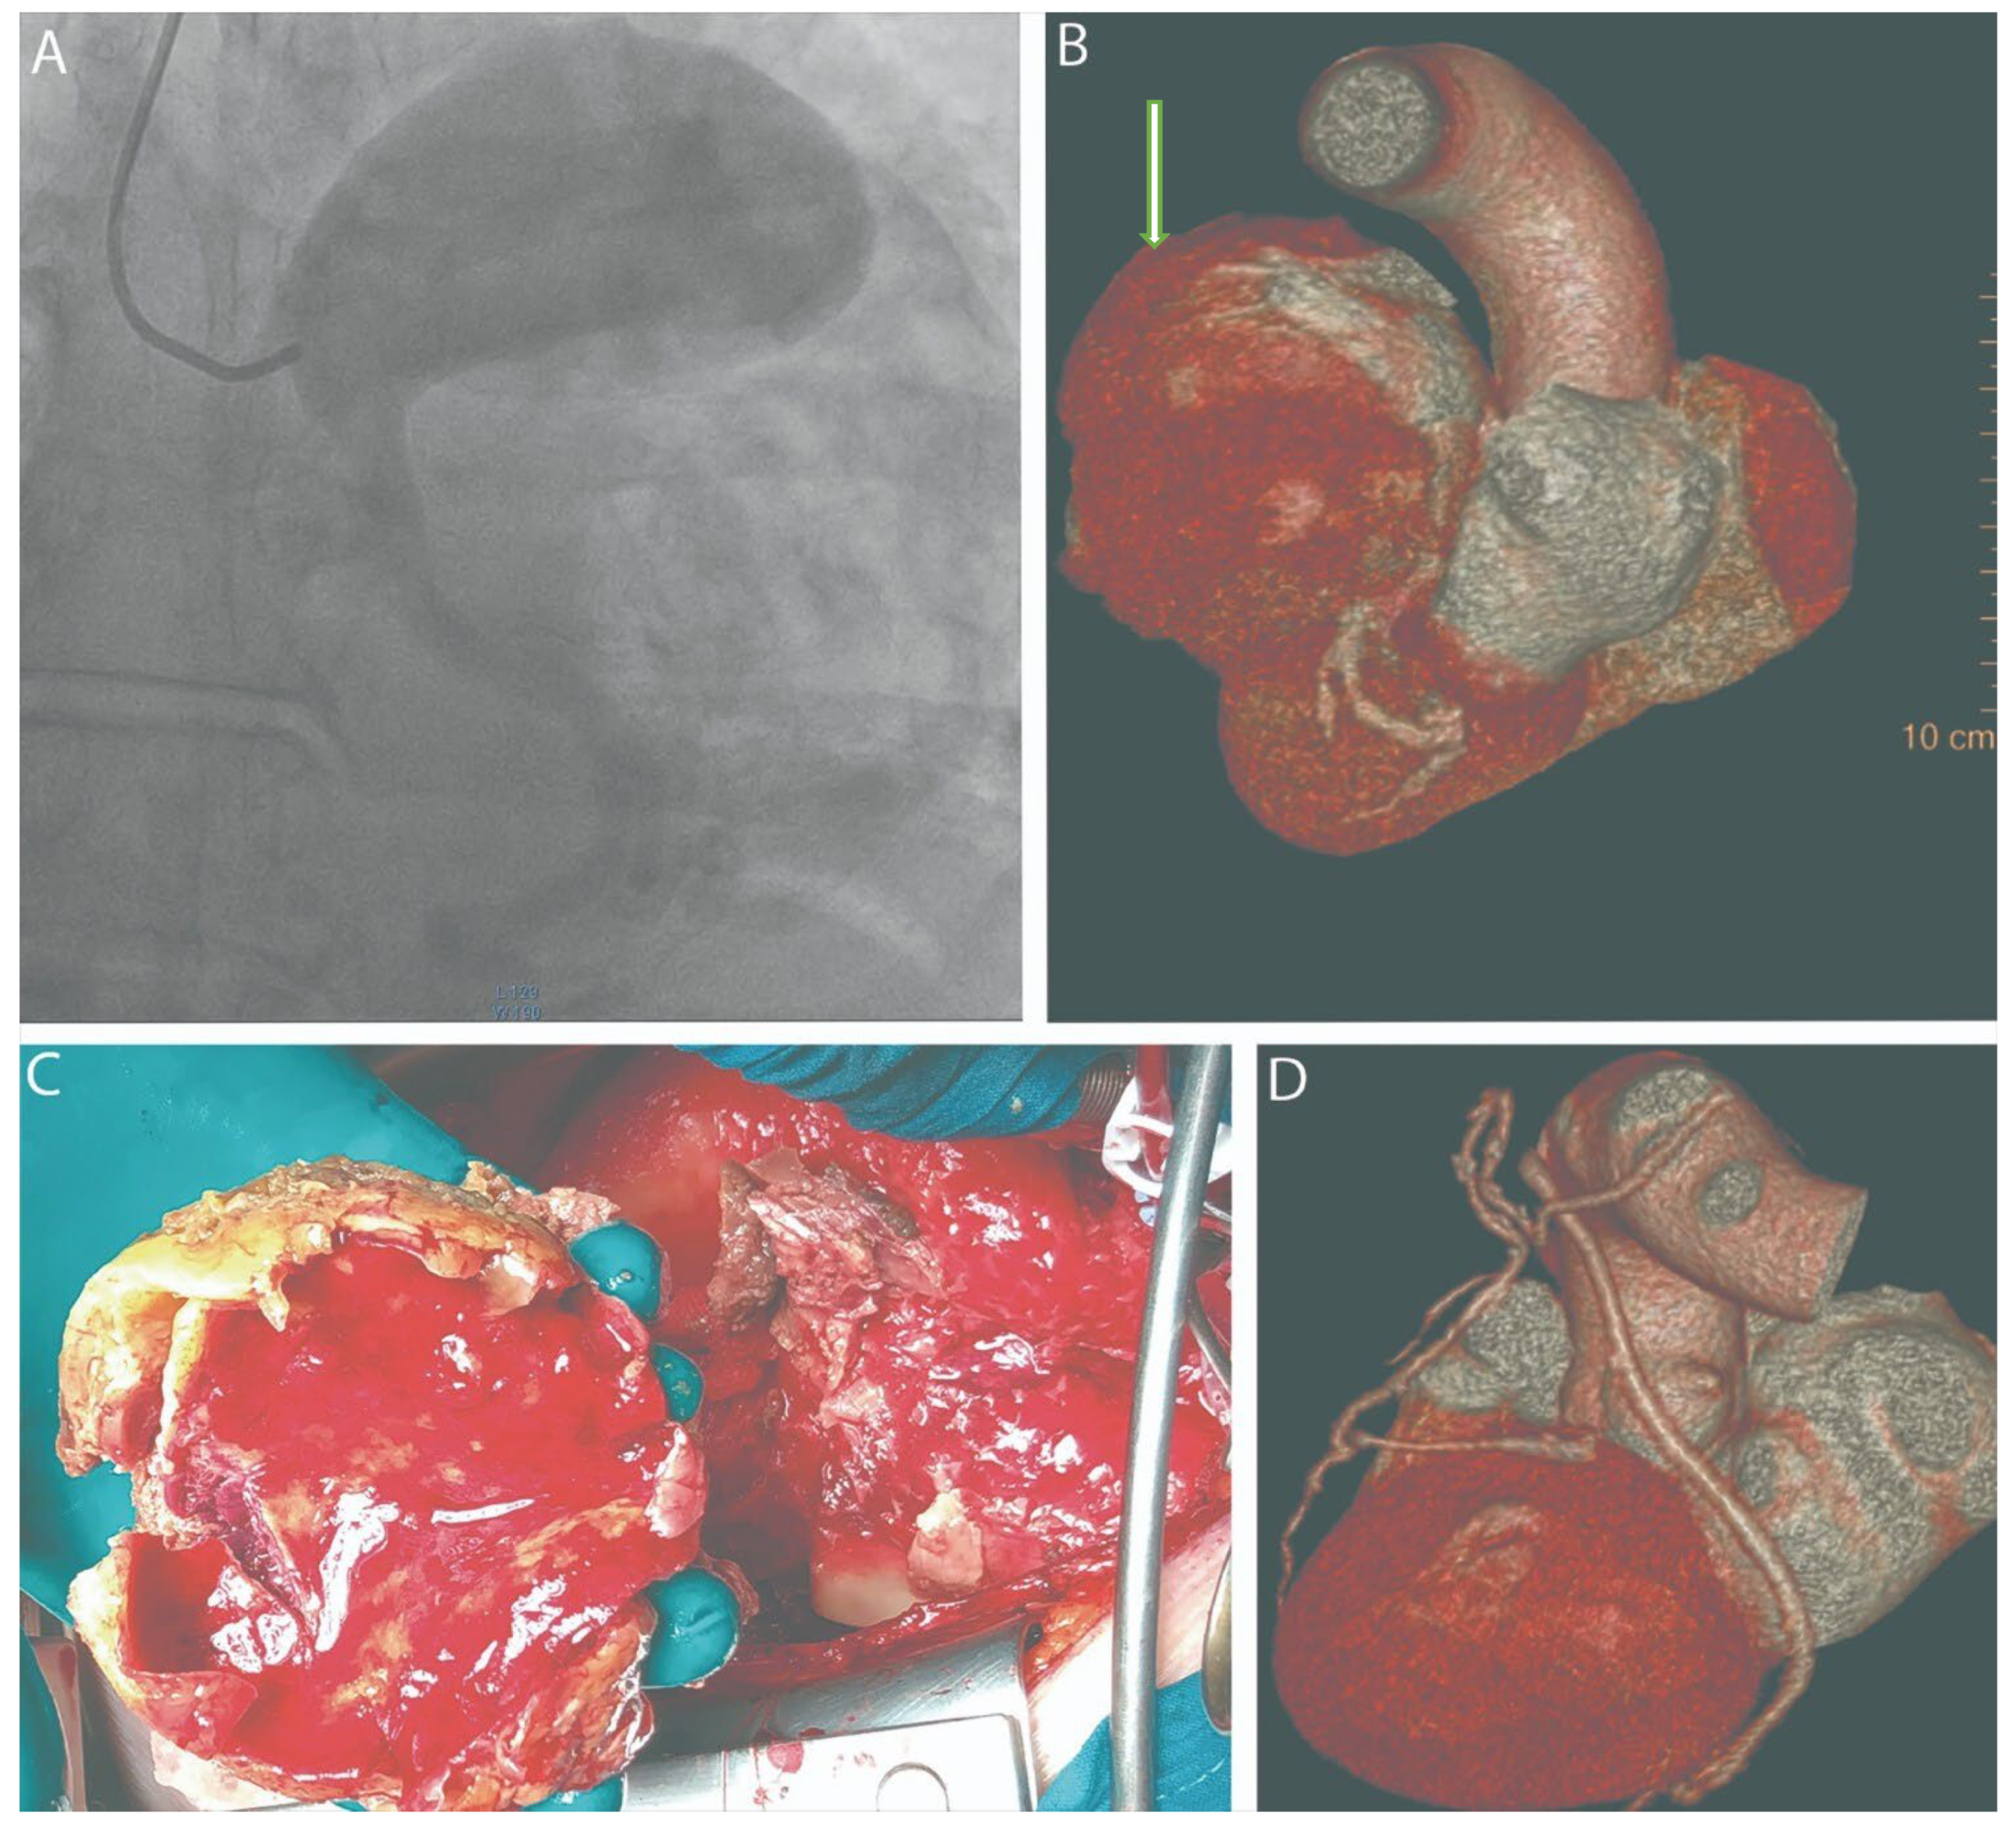

Surgical Management of a Ruptured Giant Left Main Coronary Artery Aneurysm Presenting with Cardiac Tamponade

Shumakov, D.; Zybin, D.; Stepanova, E.; Dabravolski, S.; Sigaleva, E.; Silina, E.; Stupin, V.; Popov, M. Surgical Management of a Ruptured Giant Left Main Coronary Artery Aneurysm Presenting with Cardiac Tamponade. Diagnostics 2025, 15, 2302. https://doi.org/10.3390/diagnostics15182302